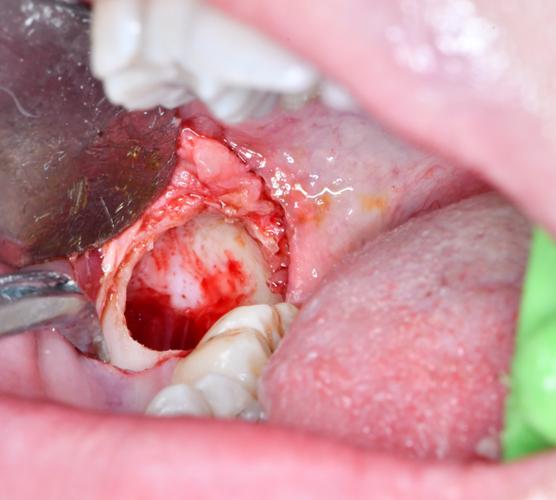

- 翻瓣:

- 用牙龈分离器或15号刀片沿切口线切开黏膜、骨膜。

- 用骨膜分离器(或专用翻瓣器)小心地掀起黏骨膜瓣,暴露下颌升支前外侧及磨牙后区的骨面。操作需轻柔,避免舌侧软组织撕裂(舌侧组织较薄,易撕裂出血)。

- 去骨:

- 目的: 暴露牙冠,去除覆盖在牙冠表面的骨组织(覆盖骨)。

- 工具: 高速涡轮机(配备合适的圆头或球钻车针)或超声骨刀(更微创,对软组织损伤小)。

- 操作: 在阻生牙牙冠上方及颊侧、舌侧(根据需要)去除适量骨质,形成骨窗,直至牙釉质暴露。注意保护下颌管神经(CBCT已定位),去骨量要足够但不过多。